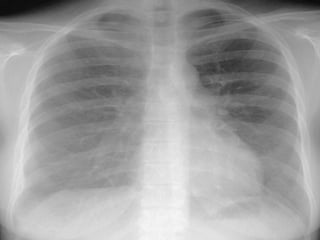

Clinical Observations Chest Wiggle Factor  CXR T8-9 Pulse oximetery TCO 2 ABG

Clinical Observations ChestWiggle Factor CXR T8-9 Pulse oximetery TCO 2 ABG